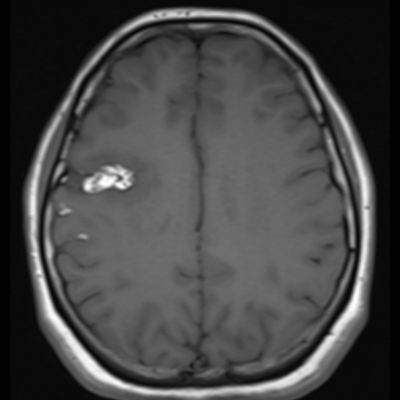

29 yaş, K

Baş ağrısı

Arteriyovenöz Malformasyon

AVM